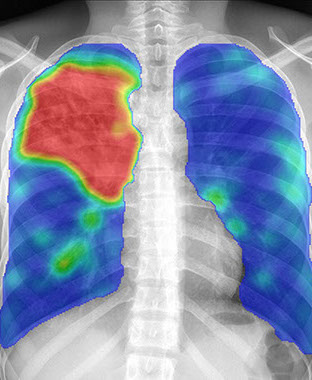

X-Ray 4 TB Health PNG

To help this we are wanting to donated a TB Digital X-Ray Diagnostic System & Analyzing system that will find and will allow treatment for people with TB. This process take less than two minutes per scan and the system refreshes for another assessment.

MRN and Rotary will donate a  Digital TB Detection Software, Laptop PC and Hard Drives and together with training we will work with PNG Rotary Clubs, and local hospitals and authorities to achieve a better out come for more people.

The above images show a normal Digital

X-ray and then the results of TB detection